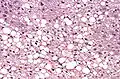

Histologically, steatosis is physically apparent as lipid within membrane bound liposomes of parenchymal cells.[2] When this tissue is fixed and stained to be better viewed under a microscope, the lipid is usually dissolved by the solvents used to prepare the sample. As such, samples prepared this way will appear to have empty holes (or vacuoles) within the cells where the lipid has been cleared. Special lipid stains, such as Sudan stains and osmium tetroxide are able to retain and show up lipid droplets, hence more conclusively indicating the presence of lipids. Other intracellular accumulations, such as water or glycogen, can also appear as clear vacuoles, therefore it becomes necessary to use stains to better determine what substance is accumulating.

Histological section of a mouse's liver showing severe steatosis. The clear vacuoles contained lipid in life; however, histological fixation caused it to be dissolved and hence only empty/clear spaces are seen.

Histological section of a mouse's liver showing severe steatosis. The clear vacuoles contained lipid in life; however, histological fixation caused it to be dissolved and hence only empty/clear spaces are seen. Micrograph of fatty liver showing lipid steatosis. H&E stain.